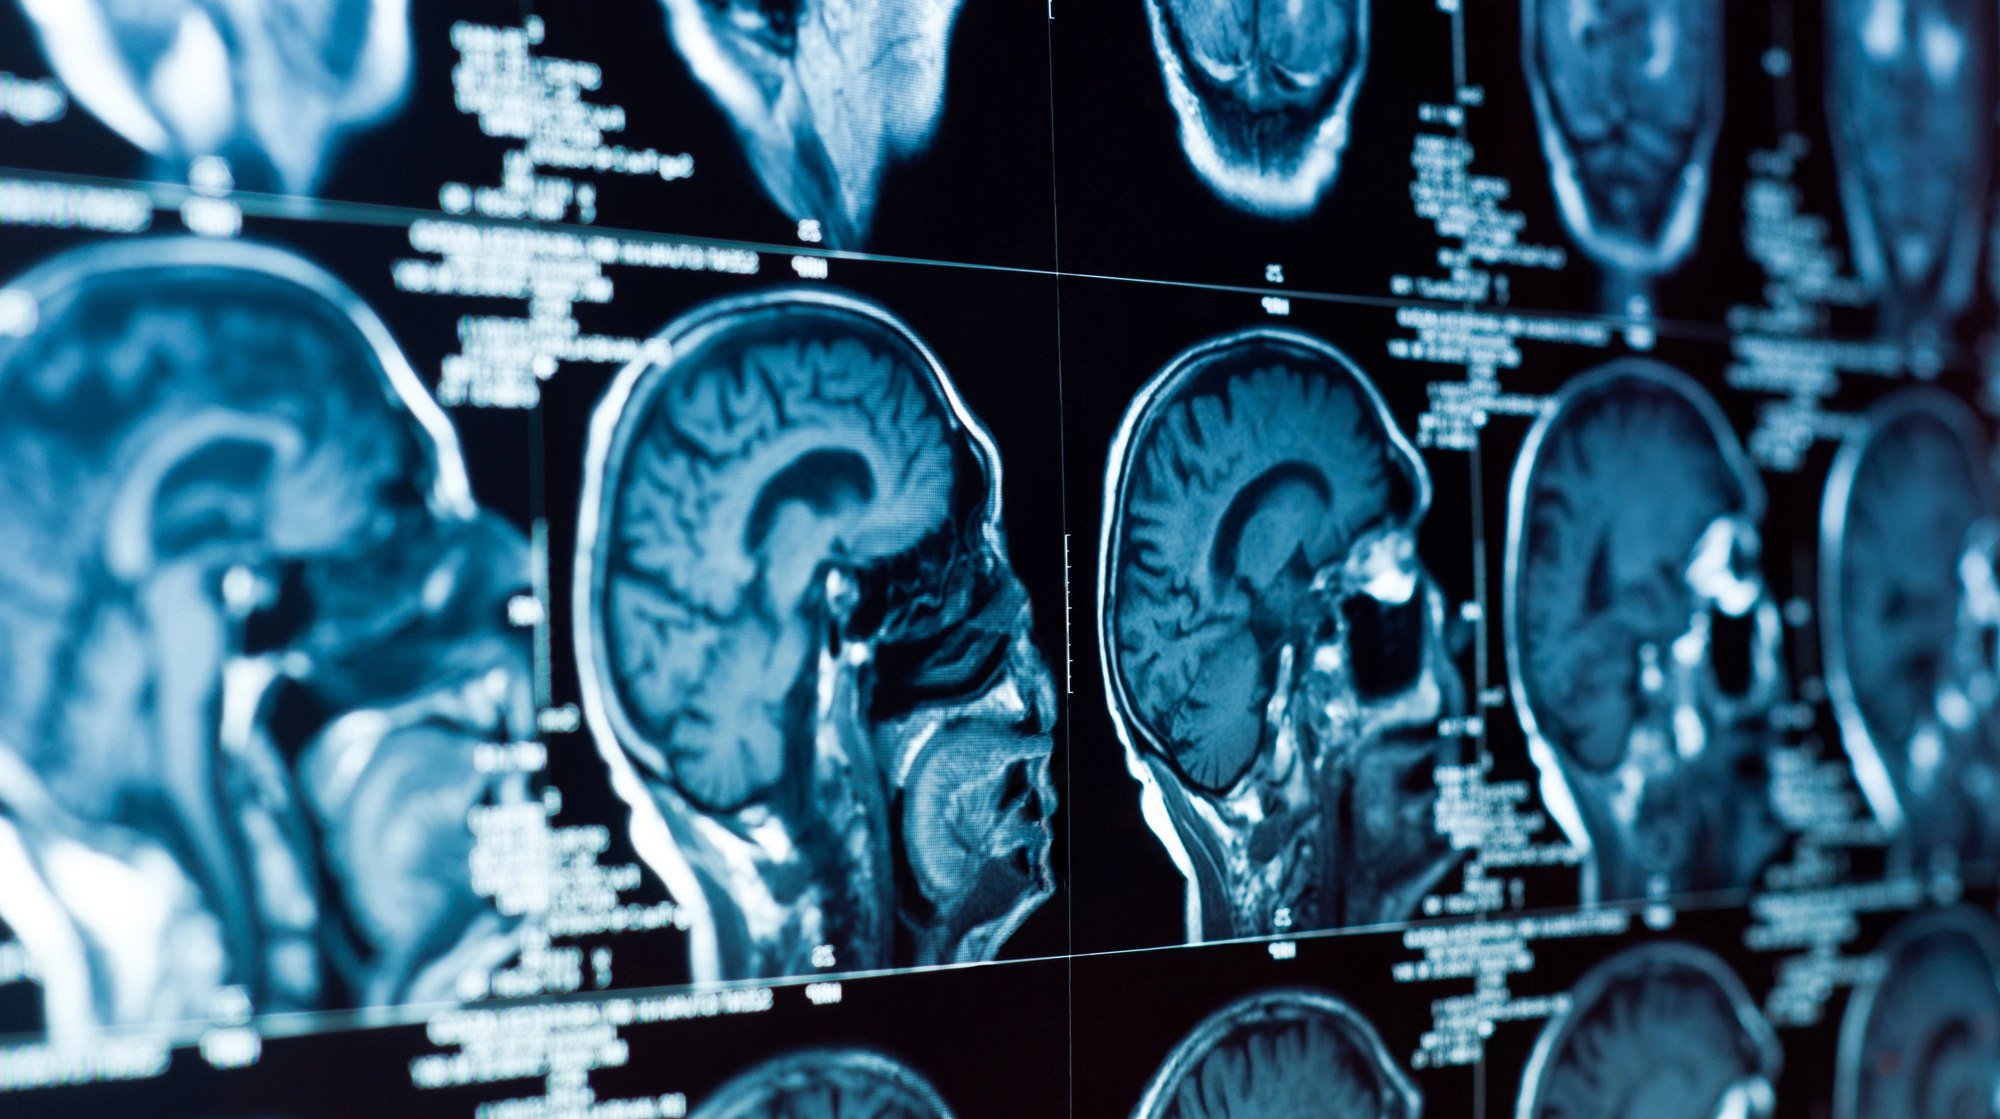

Подвоїти шанси розвитку деменції серед чоловіків старшого віку можуть дві копії варіанта гена HFE. Ця частина ДНК бере участь у регулюванні рівня заліза в організмі, вона поширена серед людей європейського походження.

Автори роботи шукали в їхній ДНК варіанти гена HFE. Вони виявили, що чоловіки з двома копіями варіанта p.C282Y цього гена можуть розвинути гемохроматоз. Це стан, який спричиняє надлишок заліза в організмі, що може стати причиною цирозу, раку печінки, крихкості кісток, артриту та деменції.

«Наявність лише однієї копії цього варіанта гена не впливає на здоров’я людини та не збільшує ризик розвитку деменції. Однак ми виявили, що дві копії більш ніж подвоюють шанси деменції у [раніше здорових] чоловіків, але не в жінок», – пояснив співавтор дослідження Джон Олінік з Медичного дослідницького інституту Кертіна в Перті (Австралія).

За підрахунками вчених, серед учасників дослідження у 2,39 раза вищі ризики деменції були в тих чоловіків, які мали дві копії гена, порівняно з тими, хто не мав жодної. У жінок такого зв’язку не виявили.

Дослідження ґрунтується на попередніх роботах про те, що варіанти гена HFE можуть впливати на деменцію. Хоча варіант p.H63D також може пошкоджувати мозок, на відміну від p.C282Y, він не спричиняє перевантаження організму залізом.